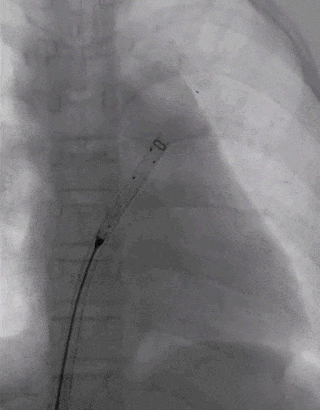

建立输送轨道

导管导丝送入左上肺静脉

加硬导丝送入左上肺静脉,送入14F输送鞘

送入BDASD-I 14可降解ASD封堵器

展开左右盘面

左盘展开

右盘展开

锁定与牵拉试验

释放封堵器